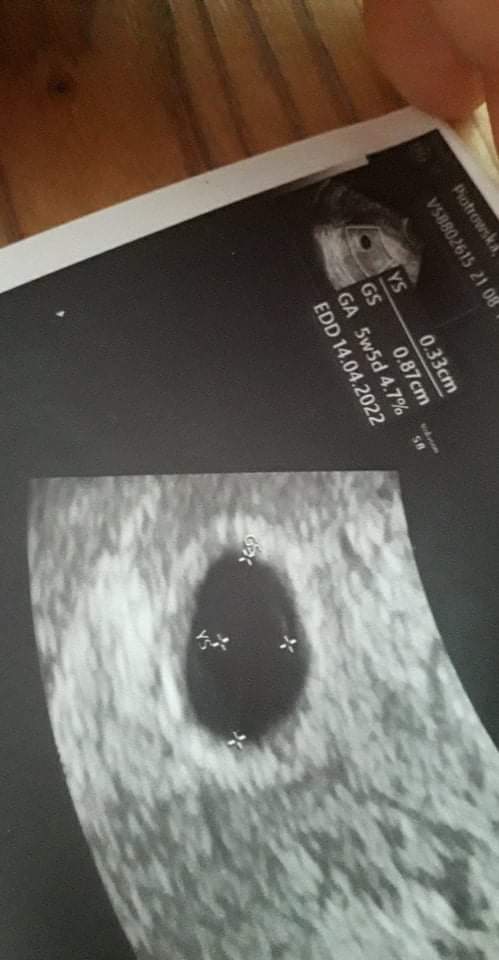

Witam, nie dawno dowiedziałam się o ciąży. Lekarz powiedział że jestem w piątym tygodniu ciazy, pecherzyk ciążowy i zółtkowy jest ale brak jeszcze zarodka. Od razu łzy ale jak to? Następna wizyta dopiero za dwa tygodnie, lekarz tłumaczy, ze to wczesna ciąża, ale strach jest duży, wyniki GS=0.87CM, a YS=0.33cm. Czy któraś z Was ogarnia te wyniki coś może powiedzieć? Albo sama miała podobne przeżycie? Zobacz załącznik 1307335

Ja w 5tc miałam gs=1.08, ys=0.30. Lekarz mówił że za kilka dni powinien być zarodek.

Dokładnie tydzień później w 6tc pojawił się zarodek i serduszko

To ja wymiary GS 0.87 a YS 0.33. I mam nadzieję że u mnie też będzie już widać, chociaż martwi mnie słabo widoczny ten pecherzyk zółtkowy, ale skoro lekarz to wymierzyl to ufam ❣